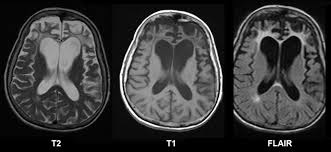

Lewy body dementia is typically diagnosed after other conditions are ruled out and the person's symptoms best fit with the diagnostic criteria for lbd. Related online courses on physioplus. Lewy body dementia stage 2 possibilities. Ct and mri show no characteristic changes in lewy body dementia but can initially help rule out other causes of dementia. Many people also experience changes in alertness including daytime sleepiness, confusion or staring spells. Read about the symptoms and what can help. Dementia with lewy bodies appears to be the second most common form of dementia, accounting for about one in five cases. Lewy body dementia, also known as dementia with lewy bodies, is the second most common type of progressive dementia after alzheimer's disease dementia.

Lewy, the scientist who discovered them. Loss of substantia nigra hyperintensity on 7 tesla mri of parkinson's disease, multiple system atrophy, and progressive supranuclear palsy. Besides nuclear imaging methods, the clinical utility of structural neuroimaging with magnetic resonance imaging (mri) for differential comparison between dementia with lewy bodies and alzheimer's disease. You also might see things that aren't there, called hallucinations. Lbd is a term that covers two conditions that have similar. Protein deposits, called lewy bodies, develop in nerve cells in the brain regions involved in thinking, memory and movement (motor control). Certain nuclear scans of the brain, including positron emission. How is lewy body dementia (ldb) diagnosed? Dr michael firbank discusses his study using functional mri in lewy body dementia and alzheimer's disease at the newcastle university institute. Focal atrophy in dementia with lewy bodies on mri: Memory loss is not always an early symptom. Lewy body dementia (lbd) is a type of progressive dementia. Many people also experience changes in alertness including daytime sleepiness, confusion or staring spells.

Protein deposits, called lewy bodies, develop in nerve cells in the brain regions involved in thinking, memory and movement (motor control). It's rare in people under 65. Also, there is a helpline for support provided by dementia. Dementia with lewy bodies (dlb), also known as lewy body disease, is a neurodegenerative disease (a synucleinopathy to be specific) related to parkinson disease. Dementia with lewy bodies appears to be the second most common form of dementia, accounting for about one in five cases. Further research is needed to clarify the relationships among them. Some scans (ct and mri scans) look at how the different parts of the brain fit together, rather than how the parts work together. The deposits are called lewy bodies and are named after friedrich h. Dementia is the name for problems with mental abilities caused by gradual changes and damage in the brain. Lewy body dementia, also known as dementia with lewy bodies, is the second most common type of progressive dementia after alzheimer's disease dementia. Certain nuclear scans of the brain, including positron emission. This may include a magnetic resonance imaging (mri) or computed tomography (ct) scan of the brain. After alzheimer disease (ad), dementia with lewy bodies (dlb) is one of the most common types of degenerative dementia.